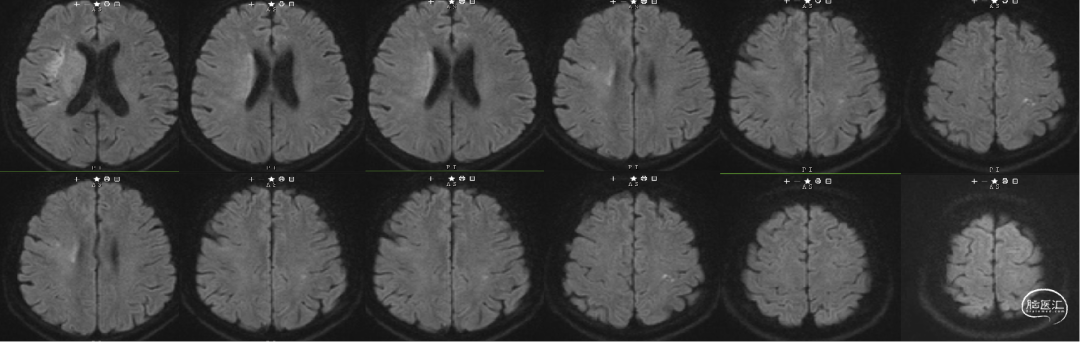

术前急诊头颅核磁共振——DWI:右侧基底节、放射冠区、左侧顶叶点状高信号